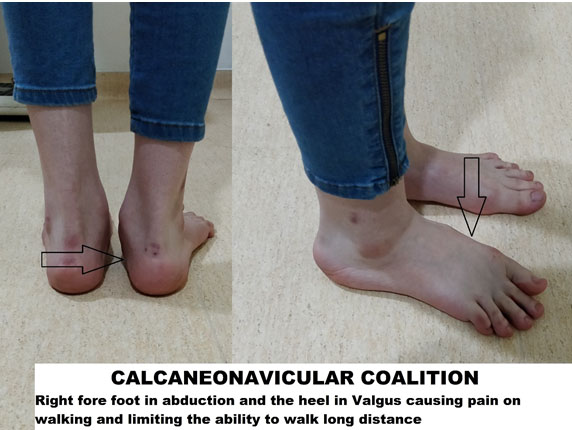

TARSAL COALITION

The coalition is an entity where there is an abnormal bony connection between bones of the hindfoot and midfoot, leading to lack of mobility in the hindfoot and thus flatfoot. Mostly it consists of two types of bony linkages called calcaneo-navicular fusion and the talocalcaneal fusion.

The calcaneo-navicular coalition is more common, and the kids are younger in the presentation (8-12 years) vs. Talocalcaneal coalition, which presents at a later age group of 12-15 years of age. The cause is primarily thought to be a failure of proper segmentation of the bone during in utero development. The coalition is noted in 1-2% of kids but is symptomatic in a far fewer number of them.

Examination

On examination, the hindfoot is in valgus, and the forefoot is in abduction or nonprofessional terms; both the heel and the front part of the foot will be pointing outwards. Patients will have a decreased speed of gait. There is a limitation in the hindfoot motion in these patients and thus find it difficult to walk on uneven surfaces.